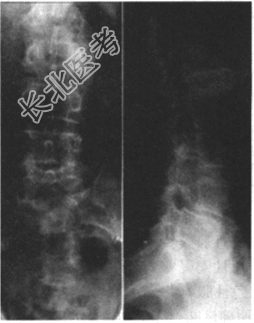

- 多项选择题3.提示:该患者的X线片如下图。该患者的诊断是

A、L4椎弓峡部裂并L4滑脱Ⅰ度

B、L4/L5椎间盘突出症

C、腰椎椎管狭窄症